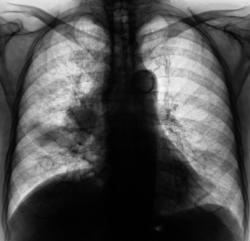

Произвели рентгенограммы в прямой и правой боковой проекциях.

Средняя доля уменьшенна в объёме, пневмония в S4.Явно изменена структура корня справа( по прямому снимку). Деформация лёгочного рисунка, не исключаеться концероматоз.Предворительно: центральный рак правого лёгкого?, осложнённый параканкрозной пневмонией в S4.Канцероматоз?? Показаны томограммы на структру корней.

Центральный Cr правого легкого. Параканкрозная плевропневмония в S4.

...перибронхиальная форма

Конечно налицо картина центрального рака правого главного бронха с разветвленным перибронхиальным ростом, лимфангитом справа, метастазами в лимфоузлы правого корня. Насчет параканкрозной пневмонии - неверное более справедлив термин - обструктивный пневмонит... В правом легком множественные ячеистые структуры - поликистоз.